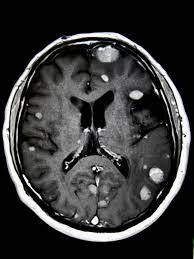

Signs Of Metastatic Breast Cancer In Brain / How Research Is Failing Women With Metastatic Breast Cancer Time : They are usually named after the tissue or organ where the cancer first developed (for example, metastatic lung or breast cancer tumors in the brain, which are the most.. Metastatic brain tumors (also termed secondary brain tumors) are made of cancerous cells that spread through the bloodstream from a tumor located elsewhere in the body. Webmd medical reference reviewed by brunilda nazario. Metastasis is most often found when people report symptoms, such as bone pain, to. Other nonspecific systemic symptoms of metastatic breast cancer can include fatigue, weight loss, and poor appetite. The incidence of brain metastasis from breast cancer (24 % in this review) is increasing due to advances in both imaging technologies leading to earlier detection of the brain metastases and introduction of novel therapies resulting in longer survival from the primary breast cancer.

Metastatic breast cancer means the cancer has spread from your breast to distant organs such as your bones, lungs, or other parts of your body. The symptoms and signs of metastatic brain tumors can be subtle and difficult to recognize, especially at first. Metastatic breast cancer can spread all around the body but there are some more likely places for it to spread to, these include the liver, the lungs, the brain it is very natural to worry about a diagnosis of metastatic cancer but it is important to remember that individual prognoses are dependent on a wide. Metastases from breast cancer can be a frequent finding in routine oncoradiological practice. Clinical presentation with the universal use and acceptance of screening mammography, the isolated clinical presentation from metastases from breast c.

An overview of the presentation, diagnosis. Webmd medical reference reviewed by brunilda nazario. Sometimes people with metastatic breast cancer do not have any of these changes. Metastatic cancer can display general symptoms and symptoms at specific sites of metastasis. Metastatic breast cancer, also referred to as metastases, advanced breast cancer, secondary tumors, secondaries or stage iv breast cancer, is a stage of breast cancer where the breast cancer cells have spread to distant sites beyond the axillary lymph. Signs and symptoms of metastasis. Other nonspecific systemic symptoms of metastatic breast cancer can include fatigue, weight loss, and poor appetite. Metastatic cancer that spreads from its original location is known by the name of the primary cancer. After lung cancer, metastatic breast cancer is the second most common cancer associated with brain metastases in the united states 1. Signs of cancer in the brain include headaches, seizures, vision changes, and dizziness. Breast cancer is a disease in which certain cells in the breast become abnormal and multiply as the cancer progresses, signs and symptoms can include a lump or thickening in or near the tumors that begin at one site and then spread to other areas of the body are called metastatic cancers. They are usually named after the tissue or organ where the cancer first developed (for example, metastatic lung or breast cancer tumors in the brain, which are the most. The cancer has spread to other parts of the body.

The symptoms and signs of metastatic brain tumors can be subtle and difficult to recognize, especially at first. The cancer has spread to other parts of the body. This usually includes the lungs, liver, bones or brain. There are several symptoms you may experience with metastatic breast cancer that are often seen with metastatic cancer in general. After lung cancer, metastatic breast cancer is the second most common cancer associated with brain metastases in the united states 1.

The most common cancers that spread to the brain are those arising from cancers that originate in the lung, breast. Sometimes, metastatic disease may not cause any symptoms. Systemic treatment of metastatic breast cancer. Metastatic brain tumors are five times more common than primary brain what are the signs and symptoms of metastatic brain tumor? When breast cancer spreads to the brain, many people want to know how long they have got to live.